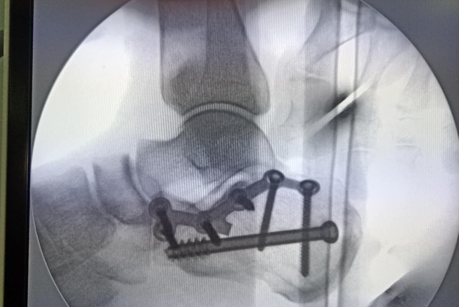

术中X线片可见骨折几乎解剖复位